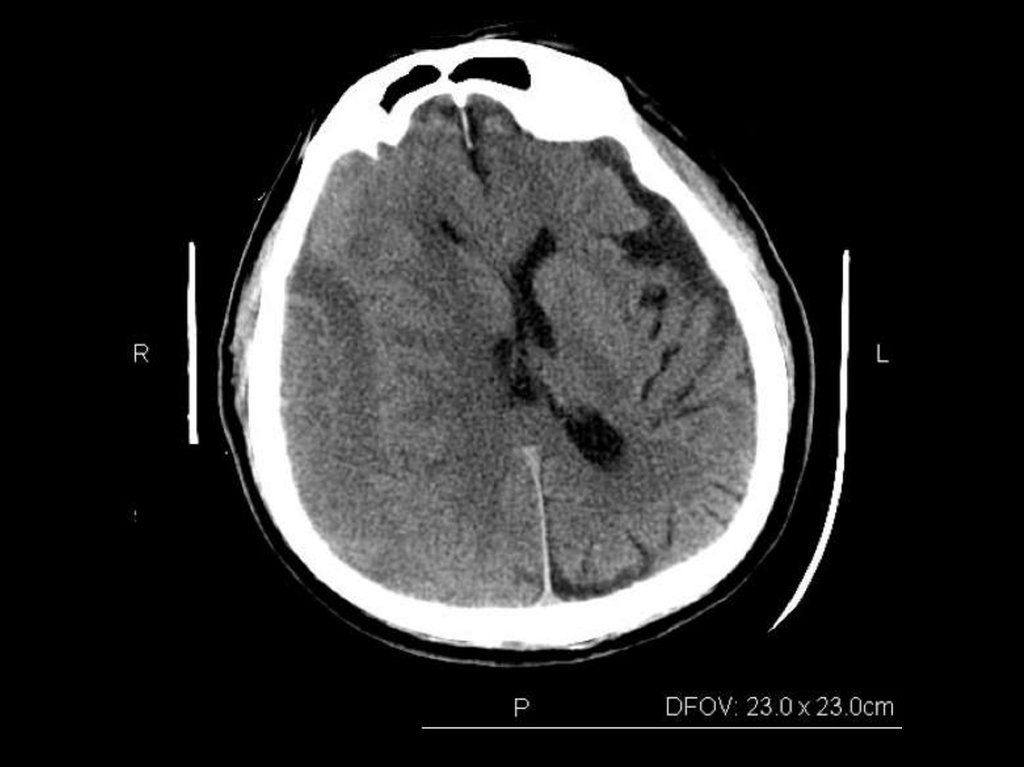

84-year-old man with a history of hypertension

Initial blood pressure of 230/120 mm Hg

12 hours after

brain death within 1 hour